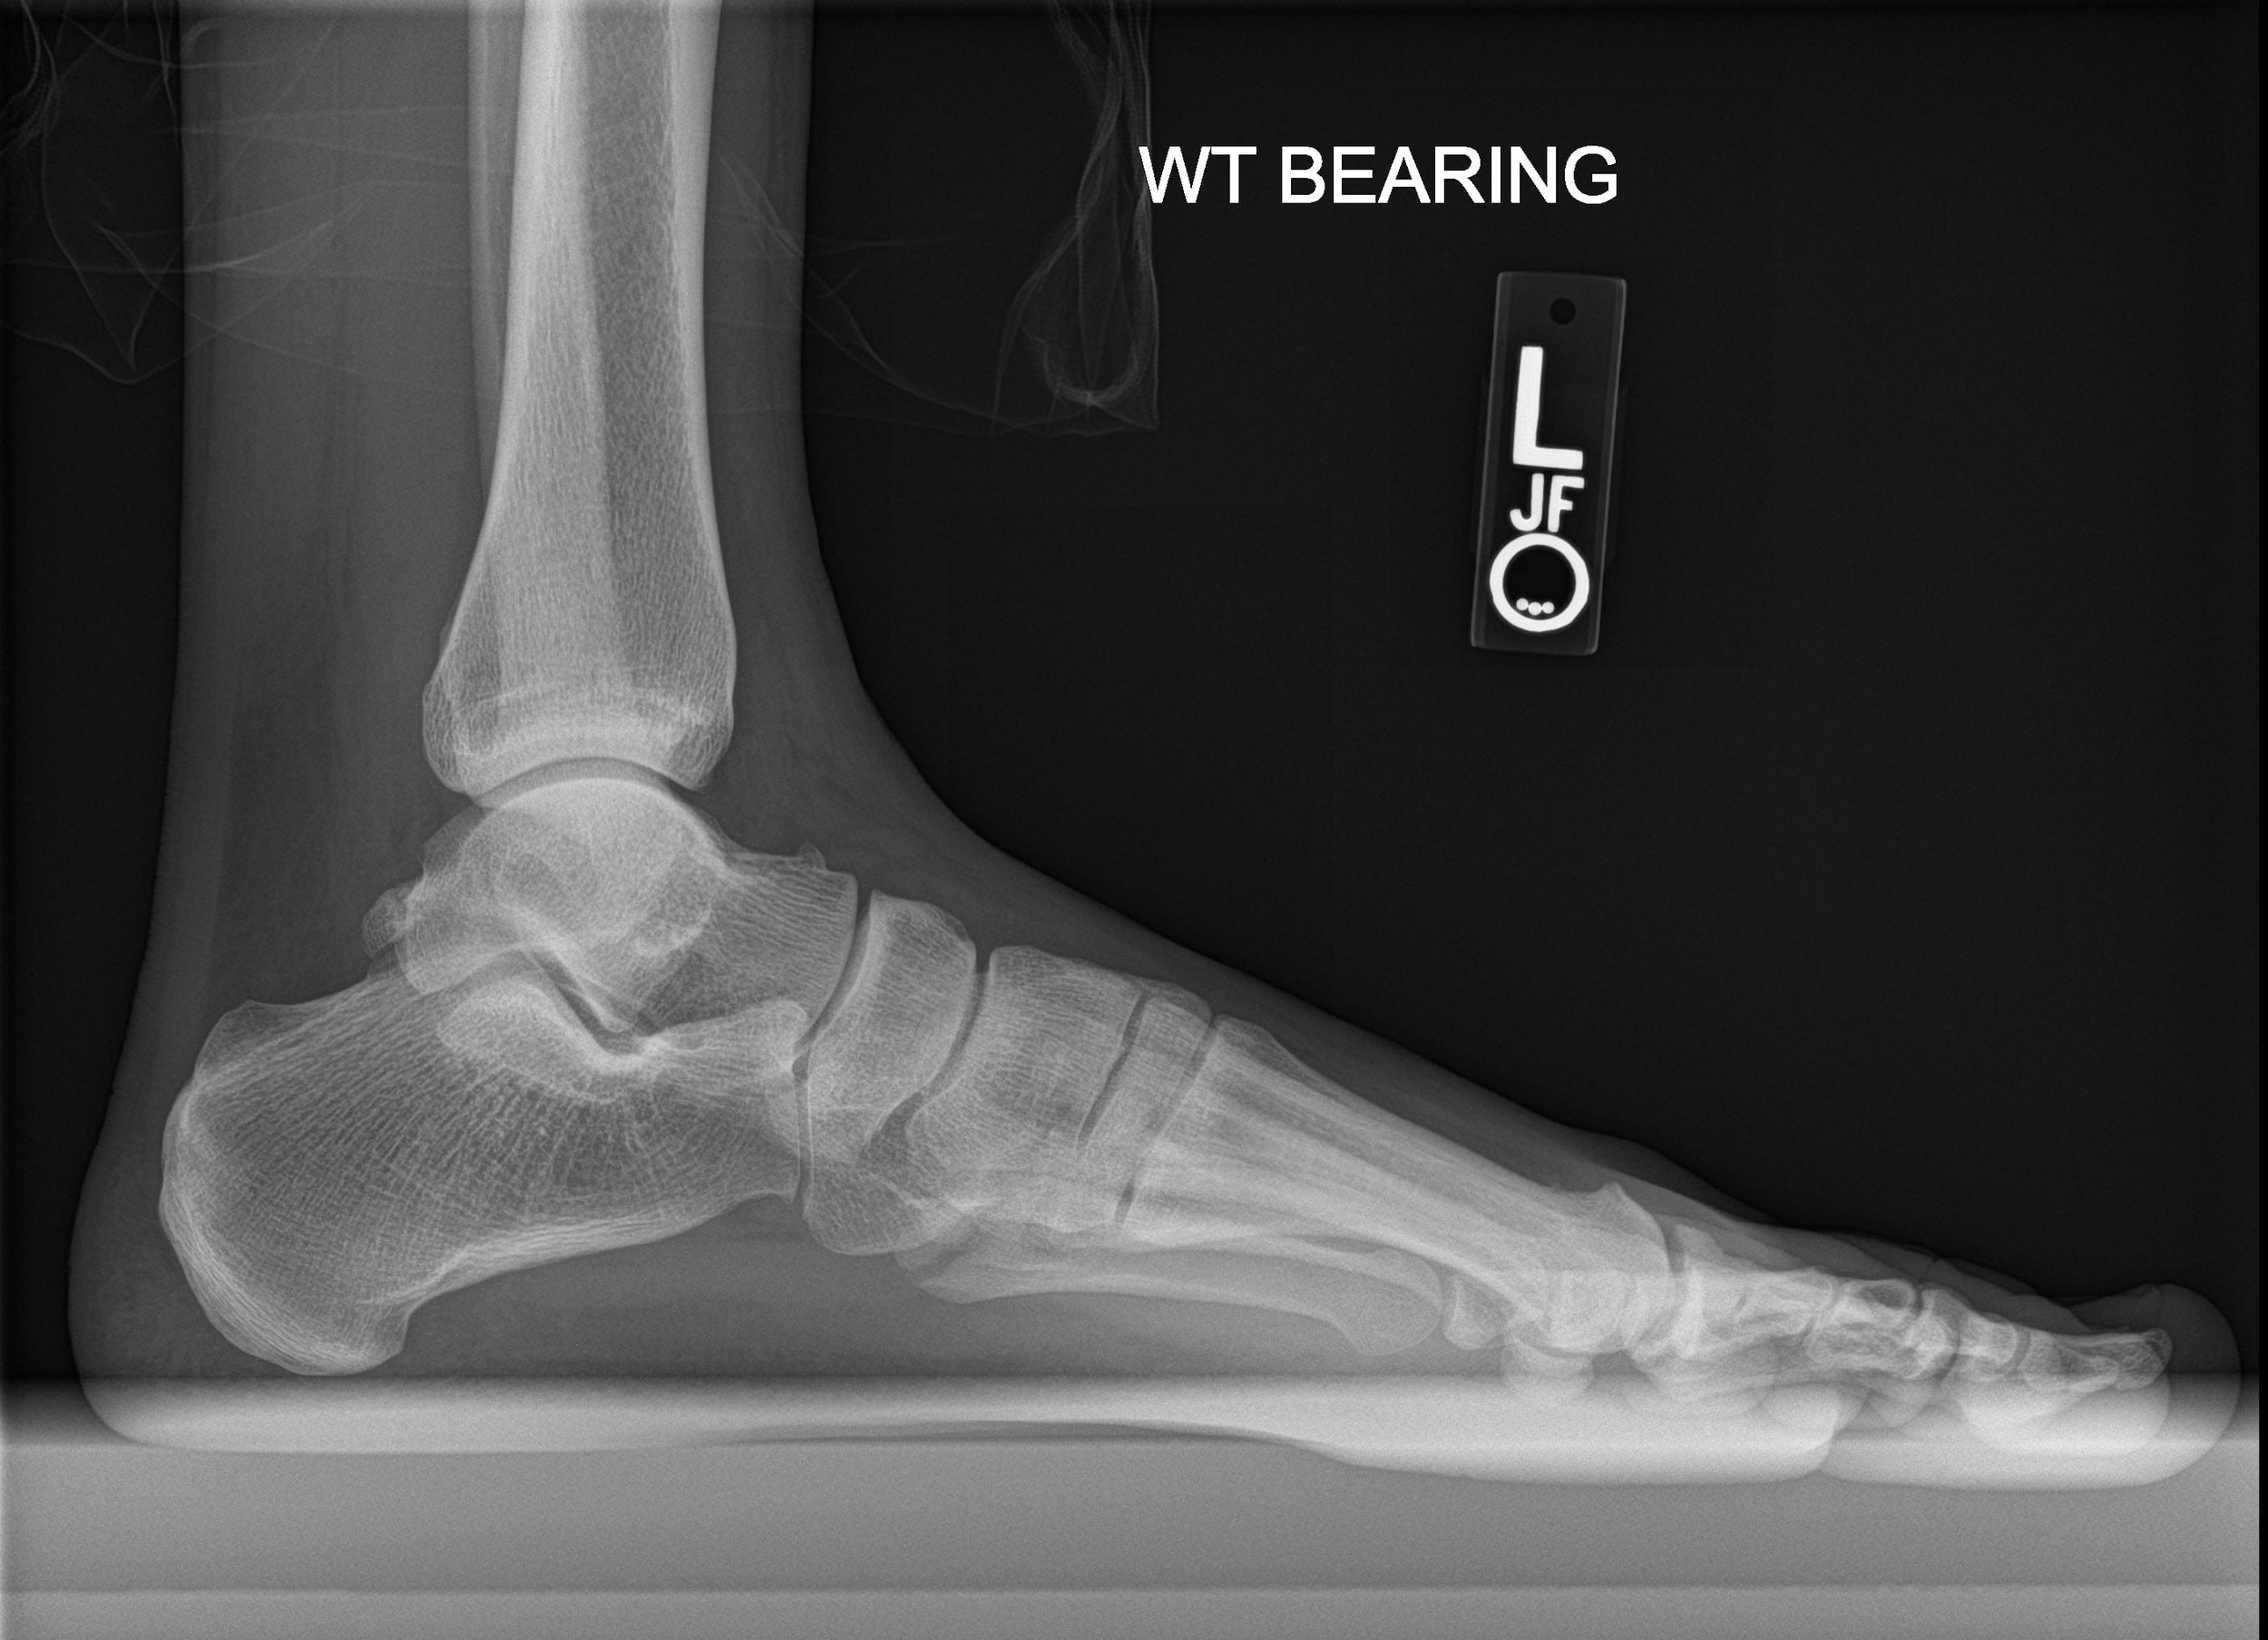

A couple weeks ago I fractured the 5th metatarsal in my foot during a game of basketball. I had just finished up a season of ski instructing in Breckenridge, CO so it was incredibly ironic to make it through the ski season without any injuries, only to break my foot while casually playing a game of pickup basketball. It was a simple diagnosis, and after four weeks in a CAM boot I should be good to go. As I got up to leave the examination room, the doctor's assistant mentioned that if I wanted to facilitate the healing process I could consider taking a calcium supplement or multi-vitamin. Historically the research has been inconclusive on whether vitamin supplementation is effective or possibly even harmful, so I decided to look into this statement a bit further.